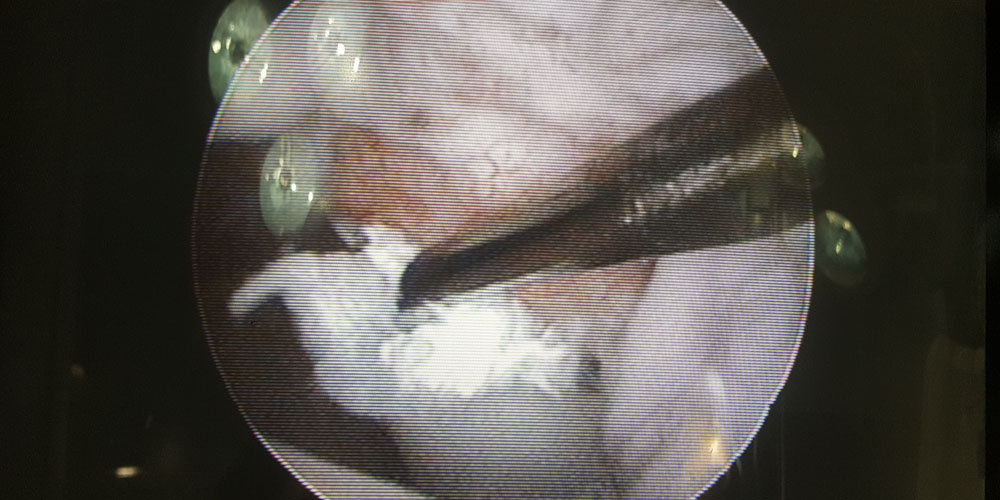

Arthrotomie/Arthroskopie

Minimal Invasive Diagnostik und Behandlung von Gelenkserkrankungen der großen Gelenke Schulter, Ellenbogen und Knie. Insbesondere Knorpel- und Knochenschäden in Schulter und Ellenbogen (OCD Osteochondrosis dissecans, FPC Frakturierter Processus coronoideus, IPA Isolierter Processus anconaeus), chronische Sehnenentzündungen der Bicepssehne im Schultergelenk und Band-/Meniskusverletzungen im Kniegelenk.